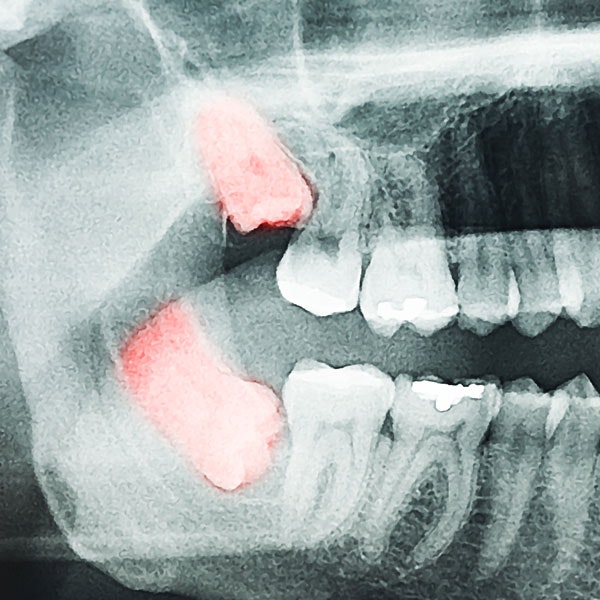

The process of extracting a tooth begins with a consultation in our Victoria, TX, dentistry office. During your consultation, our dentist will use digital x-rays and other advanced technology to accurately identify which teeth require extraction.

Receive a Surgical Extraction

The dentist may need to create an incision in the gums and remove bone tissue to access the impacted tooth for complex oral problems. In some cases, the tooth will need to be removed in pieces. Depending on the severity, you may need stitches. Again, gauze will be applied to help stop the bleeding.